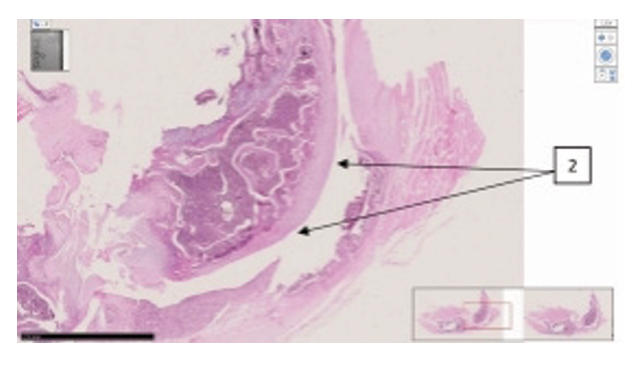

Supplementary Figure 5. Characteristic histomorphological sections of the rat knee joint. ( A) Knee joint of rat (first group with red mark). On the medial-lateral surface of the epiphyseal surface of the femur, the surface of the hyaline cartilage is somewhat uneven, the thickness of the hyaline plate is greater than usual, in the thickness of the plate near the basal layer, unevenly wavy myxomatous foci are revealed. (1). Red bone marrow is found in the metaphyseal region (2). H&E stain. Magnifications 10x10. (B) Knee joint of a rat (inducer trypsin). Sharp destructive and disregenerative changes are revealed on the lateral and medial-lateral surface of the hyaline surface of the knee joint (1), erosive-desquamative foci are revealed on the surface of the hyaline coating (2). H&E stain. Magnifications 10x10. The morphofunctional state of the knee joints of rats in the group with trypsin-induced osteoarthritis was determined at a level of 12 points on the Mankin scale. There are destructive and dysregenerative changes, damage to the components of the hyaline cartilage. As a result of microscopic examinations, symptoms of reactive synovitis and reactive arthritis were determined. This indicator indicates that the level of traumatism is very high, and the model used in the experimental conditions is recognized as highly effective in terms of alternative impact in this group.